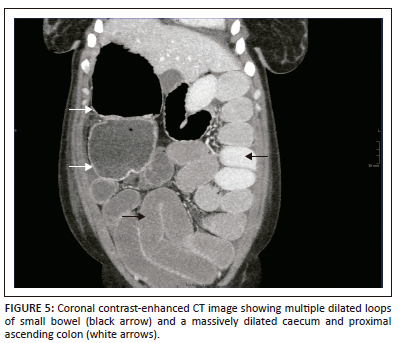

A CT of the abdomen revealed right-sided polysplenia (Figure 1) with a dominant parent spleen, a left-sided liver, extending across the midline, and a right-sided stomach (Figure 2). The superior mesenteric artery and vein were parallel to one another (Figure 3). The duodenum coursed anterior to the portosplenic vein with the duodenojejunal junction located to the left of the left-sided vertebral body pedicle but inferior to the level of the duodenal bulb, in keeping with some degree of malrotation. The jejunal loops were located in the left side of the abdomen. There was twisting of the mesentery in the right lower quadrant (Figure 4) with small bowel dilatation and massive dilatation of the caecum and proximal ascending colon (Figure 5). The transition point was within the proximal to mid ascending colon, with collapse of the large bowel distal to this point. There was also dilatation of the small bowel, most likely due to an incompetent ileocecal valve. A small amount of free fluid was noted in the right paracolic gutter and the Pouch of Douglas with multiple mesenteric lymph nodes in the right iliac fossa. Additionally, there was absence of the uncinate process of the pancreas suggestive of a truncated pancreas (Figure 3).